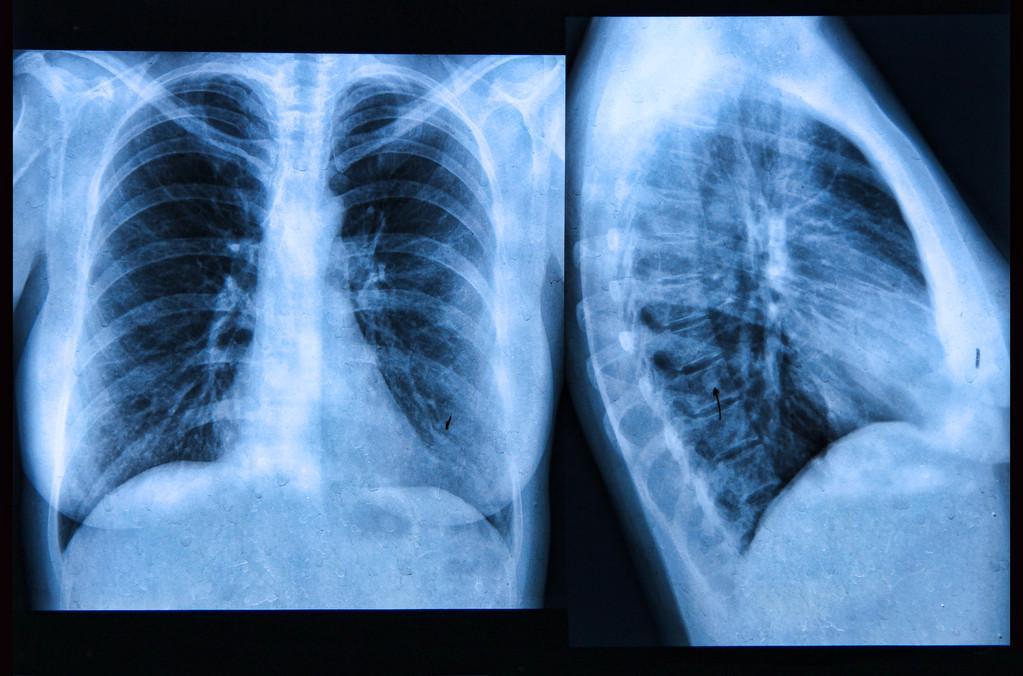

4、胸部X光检查:

胸部X光检查是一种医学检查方法,主要用于检查胸部疾病,如肺炎、肺结核等,与其他检查方法相比,胸部X光检查通常不涉及到私人部位,但是仍可能令一些人感到尴尬。

1、穿着不方便:在进行X光检查时,患者需要脱掉上身的衣物,穿上一件X光透视服或裸露上半身,对于一些人来说,穿着不方便可能会令人感到尴尬。

2、年龄和性别问题:胸部X光检查通常需要暴露上半身,对一些女性来说,会感到不舒服和尴尬,另外一些人可能会担心,检查结果会透露出自己的年龄或性别等个人信息。

3、羞耻感:即使X光检查不会涉及到私人部位,但仍可能会令人感到不自在和羞耻。一些人可能会因为自身的体形、外观等方面的原因,而感到不安和尴尬。